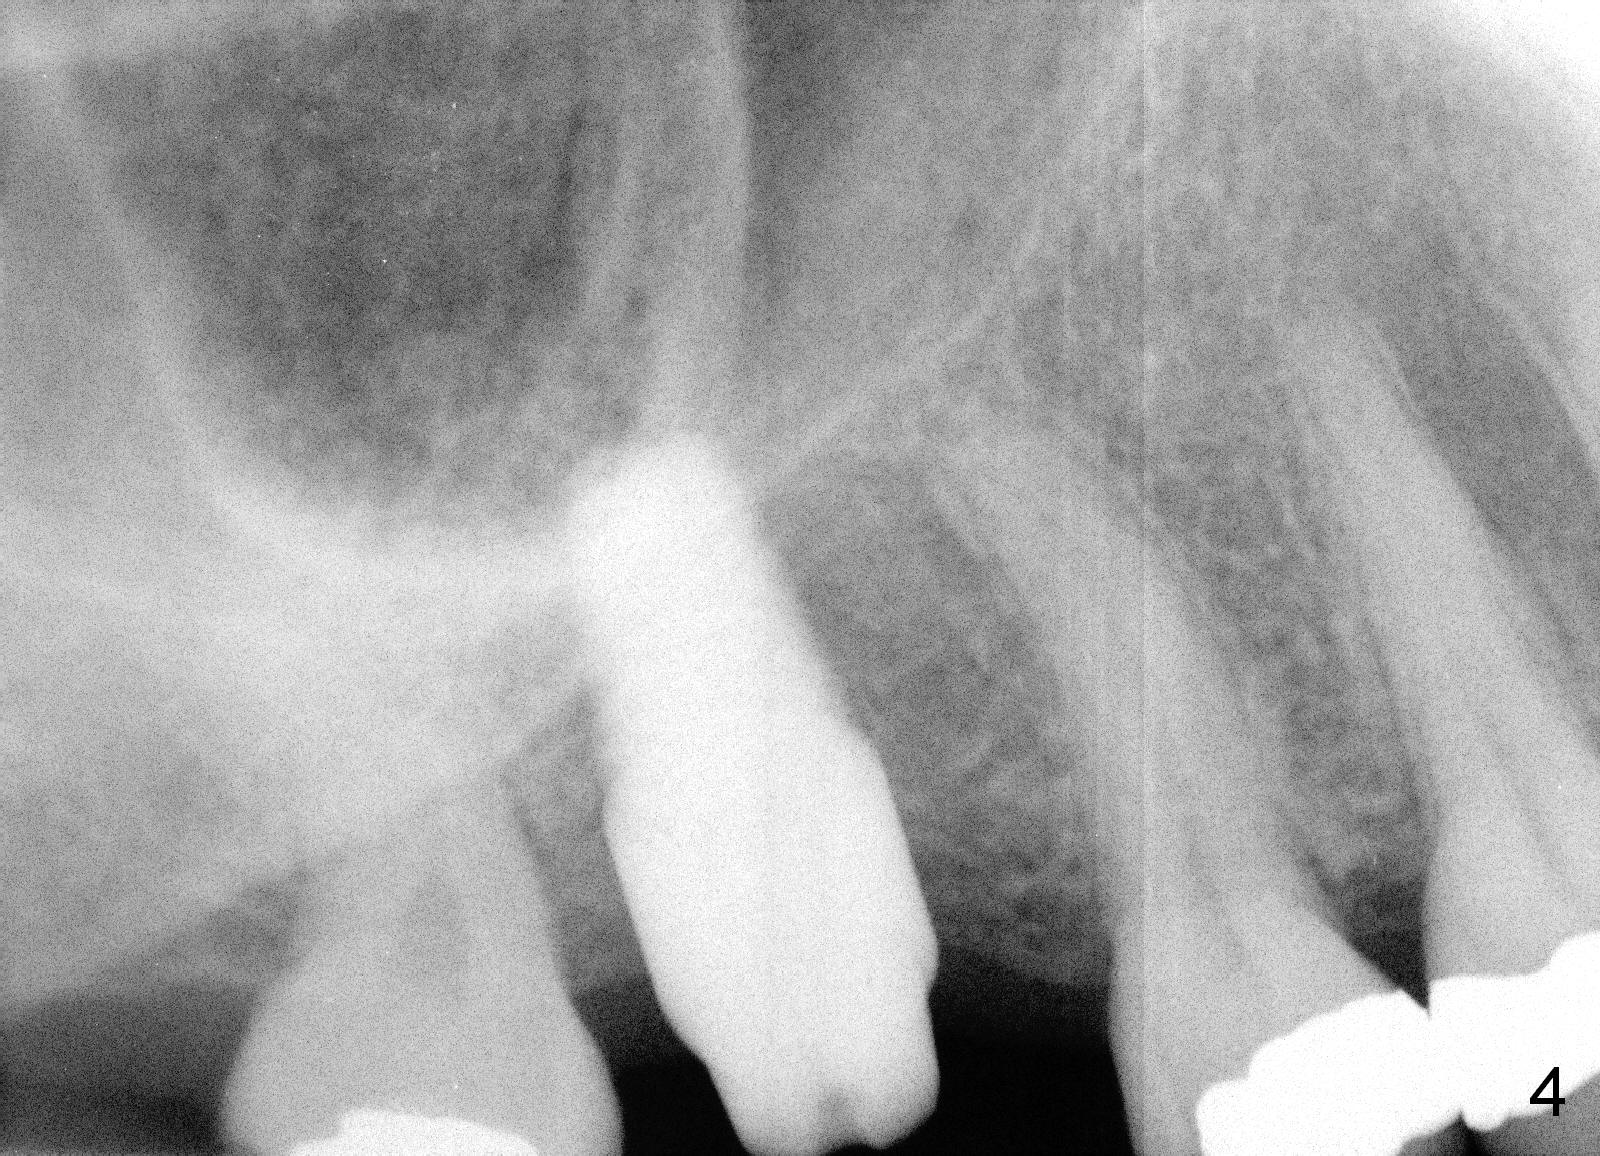

A 50-year-old lady requests implant placement at the site of #3 first. The ridge is mild to moderate atrophy. Immediately preop PA shows bone height ~ 10 mm (Fig.1 green line) and gingiva to sinus floor distance 12 mm (red line). A 10 mm incision is made over the crest. The bone is felt D3, whereas the earlier case D4. Bone expansion and condensation is still performed because it is the least invasive, no drill or suture. In brief the osteotomy is created by osteotomes, followed by taps (4.5-6 mm) (Fig.2: 4.5 mm). A 6x14 mm gingiva-level implant is placed with insertion torque of 60 Ncm (Fig.3 I). A 5x3 mm abutment (A) is placed for an immediate provisional. There is no bone resorption less than 4 months postop (Fig.4). After reprep, impression is taken for final restoration.